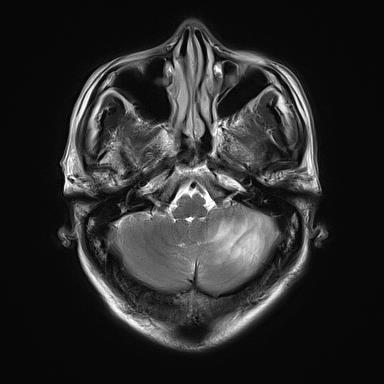

| 影像学检查:(点击查看大图) | 左侧小脑半球及蚓部异常信号,呈T1W1稍低信号,T2W1稍高信号。 |

| 患者详情: | 主因头晕、恶心、呕吐伴走路不稳1个多月。于入院1月前无明显诱因出现头晕,呈阵发性,休息后可好转,伴走路不稳。病程中患者无明显头痛、畏光、眼痛、意识丧失、意识不清、肢体无力、肢体瘫痪、眼睑下垂、多汗、面色苍白等,饮食睡眠好,大小便正常。医院行头部MRI检查示小脑多发占位性病变,临床考虑淋巴瘤可能性大。患者目前精神状态一般,体力欠佳,食欲差,睡眠正常等。 既往、个人及家族史:自诉出现药物过敏史(具体不详),表现为全身瘙痒、皮疹。2021因胆囊结石行胆囊切除术。高血压病史3年;无传染病及遗传病史。 查体:发育正常,营养良好、正常面容,查体合作。神经系统、脑膜刺激征及植物神经系统均未见异常。 手术及大体:切开左侧小脑皮层见暗红色病变,质地稍韧,血供丰富,与周围正常脑组织边界不清。术中送检(小脑占位)不整形灰红色组织,大小分别为1x1x0.4cm、1.1x0.7x0.2cm;术后送检(小脑占位)灰白色碎组织一堆,总大小为2x1.5x0.5cm。 |